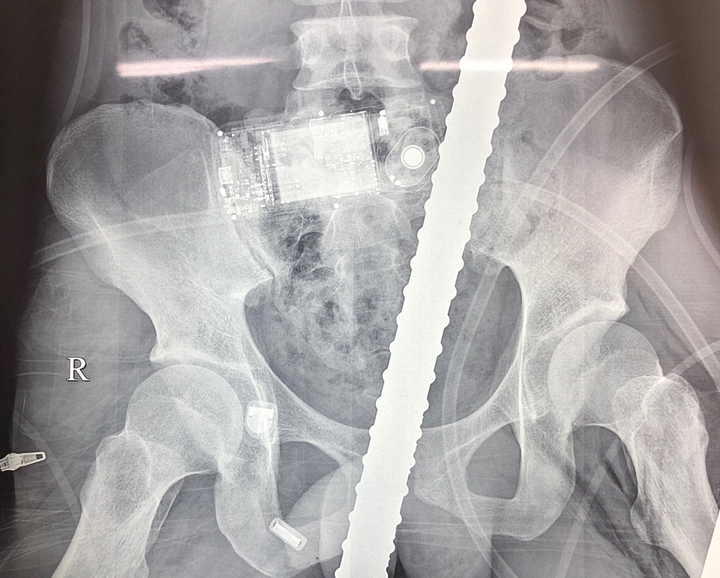

Hình ảnh X-Quang thanh sắt đâm xuyên từ đùi lên bụng bệnh nhân.

Bệnh nhân bị chấn thương đứt cơ thắt, thủng trực tràng, bàng quang, đại tràng, đứt ruột non, rách dạ dày, thủng cơ hoành trái và thành ngực trái, rách phần mềm cánh tay trái, rách cơ đùi trái, đụng dập động mạch đùi, rách tĩnh mạch đùi trái.